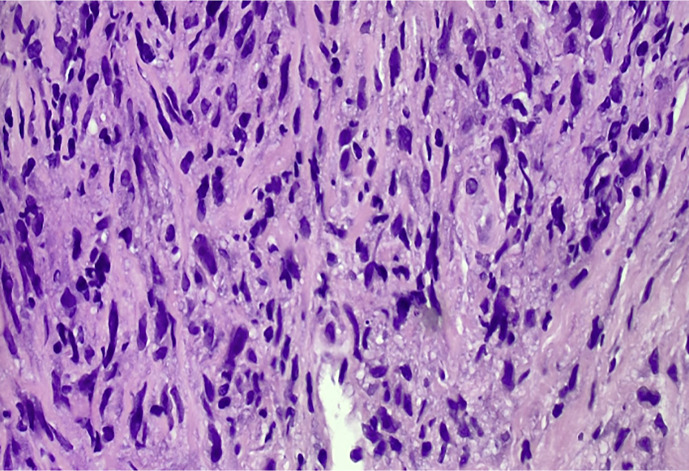

Case report: We present a rare case of PMBCL in a 39-year-old male with a bulky mediastinal mass that resulted in superior vena cava thrombosis and cardiac tamponade. Diagnostic discordance between histopathological and molecular data led to a delay in interception of this entity. Histopathology findings were suggestive of spindle-cell neoplasm. Contrastingly, next-generation sequencing (NGS) and immunohistochemistry (IHC) yielded a molecular diagnosis of PMBCL. IHC staining revealed that the atypical cells were positive for CD20, PAX5, CD79a, CD30, CD23, MUM1, and weakly positive for MAL (myelin and lymphocyte) protein. NGS showed increased expression of TNFRSF8 and CD274 genes, which encode CD30 and PDL1 proteins, respectively. The patient was successfully treated with the R-Hyper-CVAD protocol without consolidative radiotherapy.